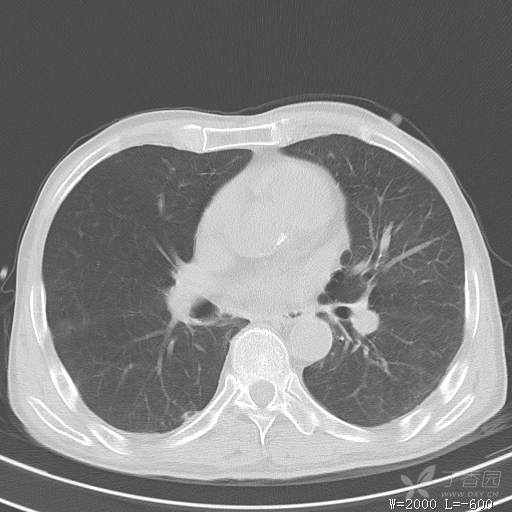

简要病史:主因发热伴腰背部疼痛2小时于2018-06-27,09:30 入院。患者无高血压,冠心病、糖尿病病史,无慢性咳喘史,不吸烟。否认食物药物过敏史。患者于入院前2小时出现发热,体温37.5℃,无咳嗽,咳痰,伴右侧腰背部疼痛,伴呕吐2次,呕吐物为黄绿色胆汁,大便2次,为稀便,无咯血,无胸闷、憋气,无鼻塞、流涕,无尿频、尿急、尿痛,就诊于我院,我院急诊查:上腹部CT:右肾结石,右下肺感染性疾病可考虑,血常规WBC13.54*109/L,GR%45.8%,急诊以“发热待查:肺感染?”收入院。

辅助检查:上腹部CT:右肾结石,右下肺感染性疾病可考虑,血常规:WBC13.54*109/L,GR%45.8%,。心肌酶示:谷草转氨酶12U/L,乳酸脱氢酶328U/L,肌酸激酶20U/L,肌酸激酶同工酶7U/L,α-羟丁酸脱氢酶277U/L,查凝血常规示:凝血酶原时间12.5秒,国际标准化比值1.07,活化部分凝血酶原时间32.6秒,纤维蛋白原浓度1.77g/L,凝血酶时间15.6秒。

临床诊断:1.腰背部疼痛原因待查:1.肺炎?2.泌尿系结石?。